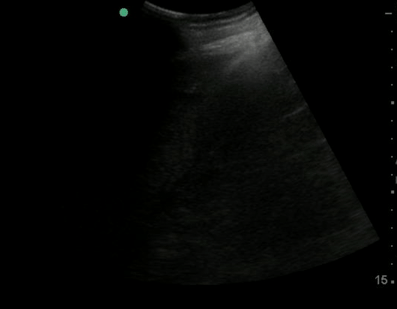

Positive fast with free fluid located at the liver tip

| current | 12:57, 18 July 2016 | 397 × 309 (1.49 MB) | Neil.m.young (talk | contribs) | Positive fast with free fluid located at the liver tip |